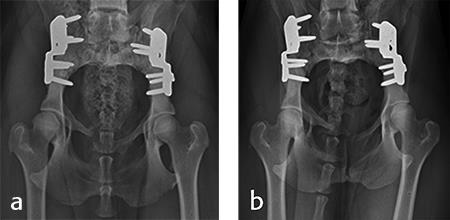

Activity was restricted to leash walks for 6 weeks postoperatively. The radiographic examination 1 month after each surgery revealed partial healing of the ilial osteotomy and stable implants. Postoperative radiographs at 6 months after both surgical procedures revealed complete healing of the ilial osteotomies, stable implants, and excellent coxofemoral conformation, with no subluxation of the femerol head. Mild osteoarthritis was observed, however. At both the 4 and 6 month evaluation, the dog was using both hind limbs without any evidence of lameness and was showing no signs of instability or pain of either hip (Fig 10).